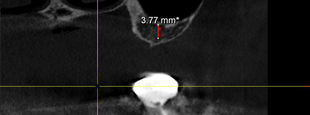

インプラント治療例

インプラントセンター歯科にて行われたインプラント手術の症例集です。